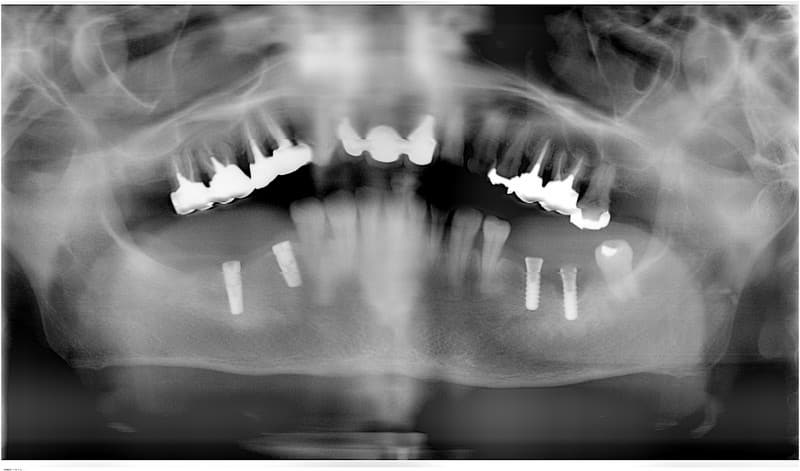

- 外科処置によって顎の骨にインプラントを埋め込みます。

- 3~6ヶ月後にインプラントに人工の歯を連結するためのパーツを取り付けます。

(小外科処置を伴います。)

技工士さんがあなただけの人工の歯をカスタムメイドで製作します。

人工の歯をインプラントに連結して完成となります。

はい。インプラントはあごの骨にしっかり結合し、その上に人工の歯が連結されますので、違和感なくほとんど自分の歯と同じ感覚がよみがえります。